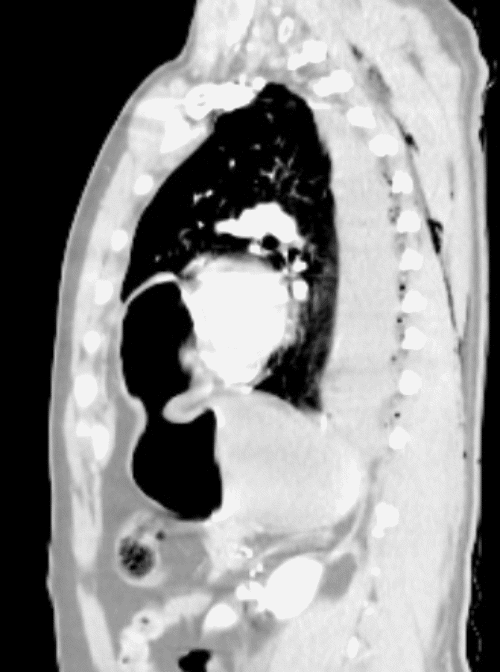

The patient's condition stabilized, and the pain was controlled with analgesia. CT showed no brain injury, but there were multiple left-sided comminuted rib fractures with displacement along the posterior and lateral aspects. In addition, it revealed the presence of hydropneumothorax; lung contusion with thoracic wall subcutaneous emphysema; right-sided mild pneumothorax; undisplaced fracture of the sternal body; herniation of the stomach into the pericardial cavity (Figure 1); no intraabdominal fluid or air and no solid organs injury; fracture of the transverse processes of the L3/L4 and L5 vertebrae; fractures of the left glenoid bone and left pelvic bone; multiple comminuted displaced fractures involving the iliac, acetabular, and pubic bones, with the displacement of the iliac bone fractures; right inferior pubic ramus nondisplaced fractures; and fracture of the left sacral alar and proximal left sacral segments (Figure 2).

Figure 1. CT of Herniated Stomach into Pericardial Space. A) Scout, (B) Axial, (C) Sagittal, and (D) Coronal Views. Published with Permission

C) Sagittal View